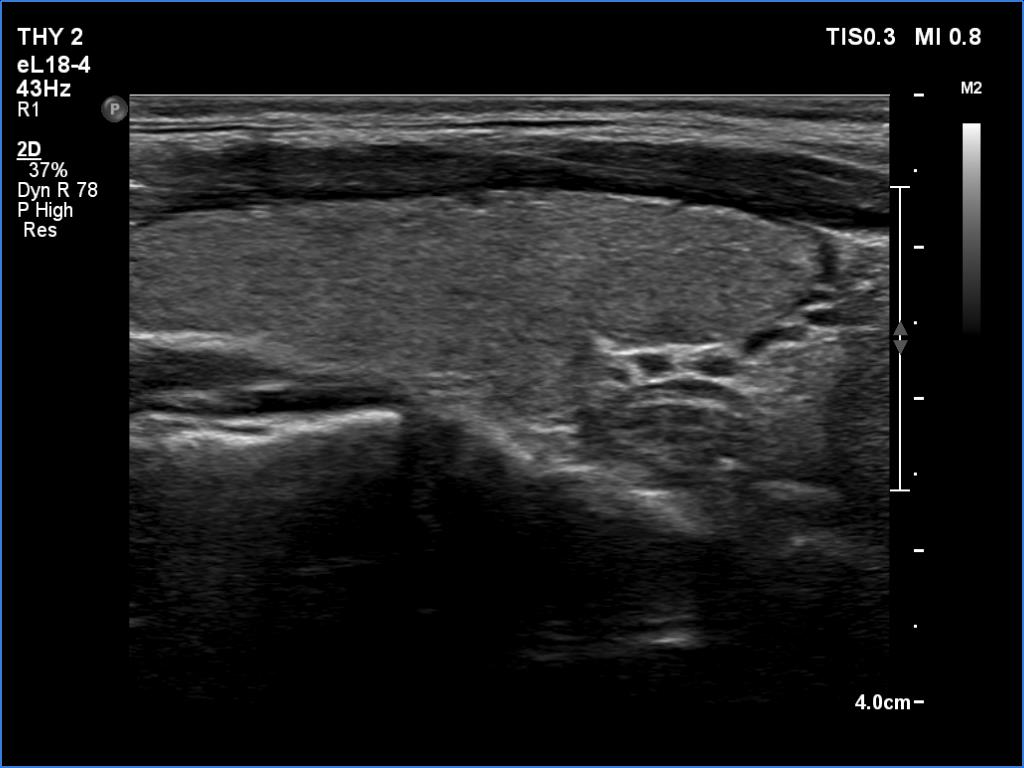

Graves' disease - case 2513 (ultrasonographic picture 2)

Right lobe, longitudinal scan

Right lobe, longitudinal scan. The thyroid does not show any signs of an autoimmune thyroid disorder.